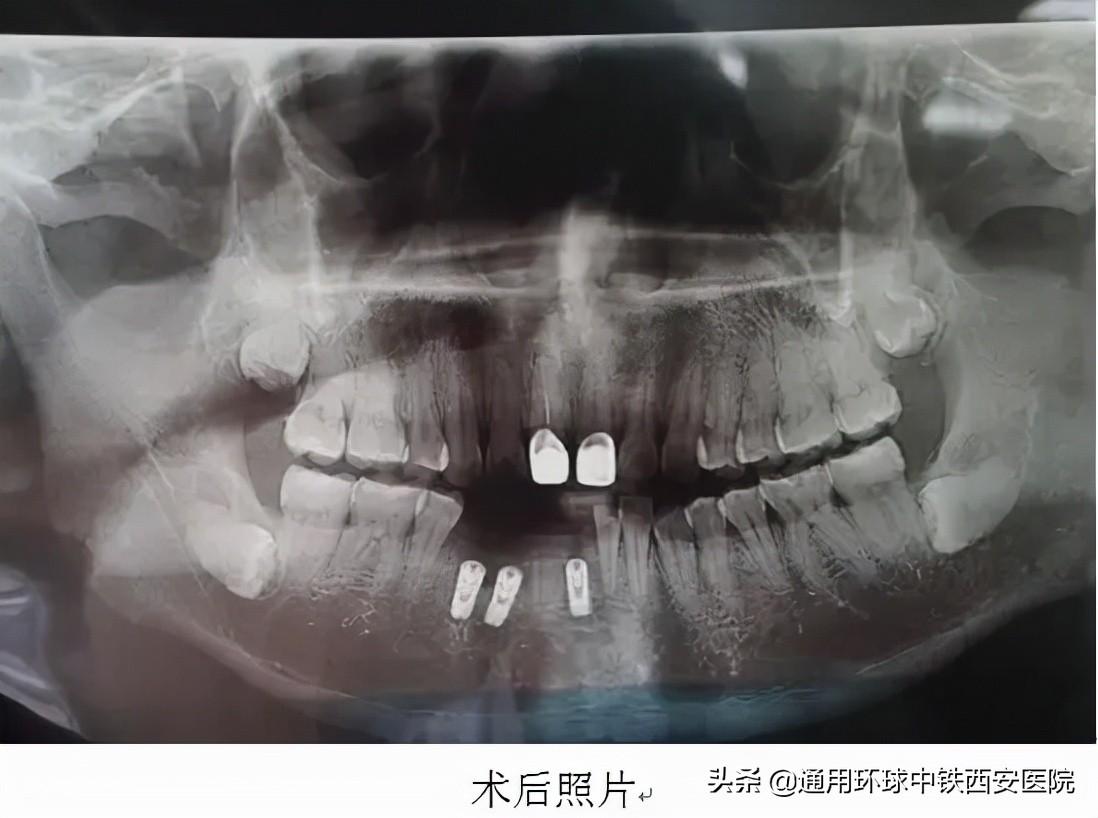

手術(shù)于9月22日進行,術(shù)前常規(guī)消毒鋪巾麻醉,微創(chuàng)拔除41、42、44牙殘根,在與術(shù)前規(guī)劃一致的位置分別植入直徑3.75mm,高度11.5mm、直徑4.2mm,高度11.5mm、直徑4.6mm,高度10mm的種植體,在唇側(cè)植入骨粉共0.25g。修整外形后。表面覆蓋可吸收生物膜,間斷嚴(yán)密縫合傷口。手術(shù)歷時約40分鐘,術(shù)后宋先生無不適。